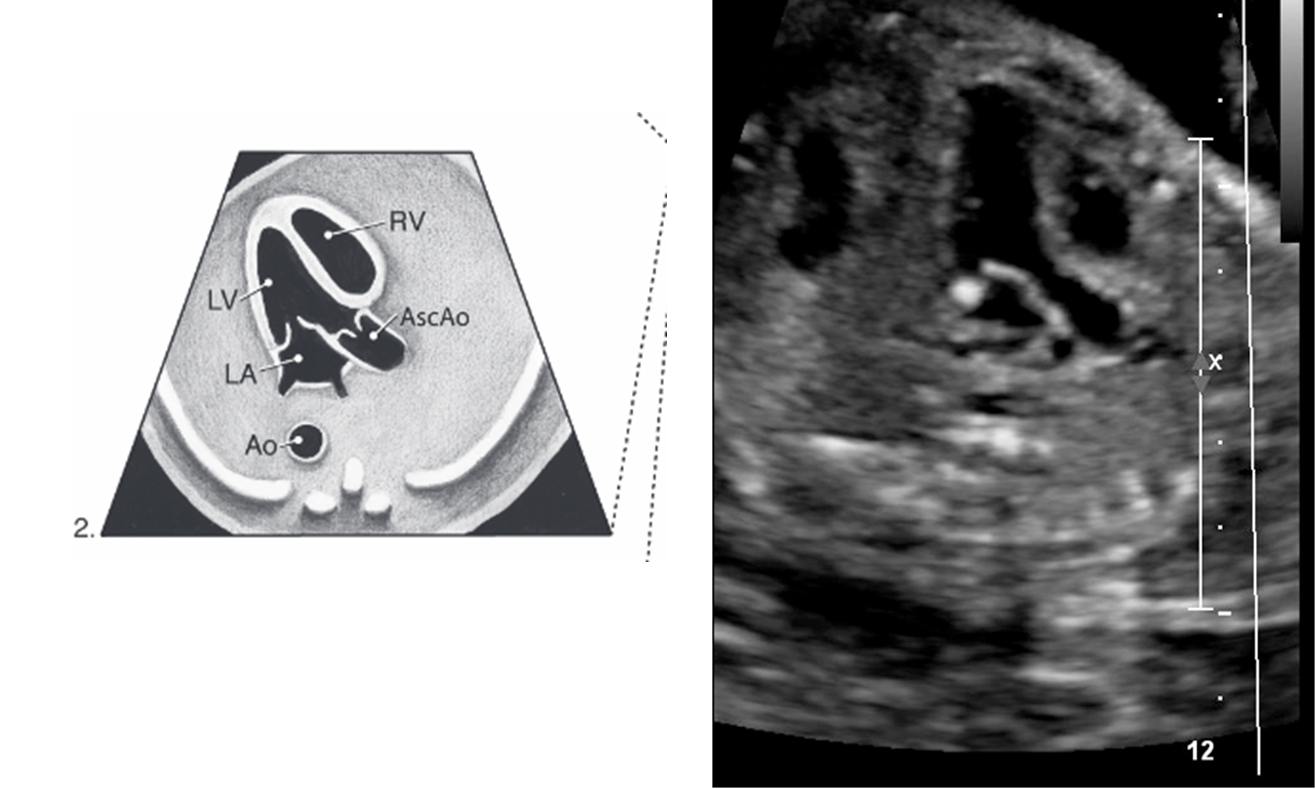

normally what is closest to anterior abdominal wall

right ventricle

what is closest to spine

left atrium

4 chamber heart should sit at a ___ degree angle and take up about ____ of the chest

45 degree

1/3

___ of the herat located in left chest with apex pointing ____

2/3

left